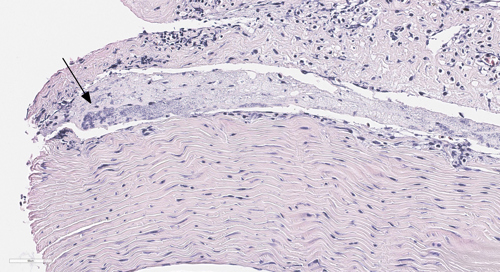

Bilde 2: Histologisk snitt. HE-farging. Bakterier og betennelsesceller (boks) i blodkar i hjerte, fra en sak med påvist Pseudomonas spp.

Infeksjon med bakterien Pasteurella spp. blir også kalt pasteurellose, og regnes som en alvorlig bakteriesykdom for oppdrettsfisk. Ved utbrudd av sykdommen, rammer det ofte stor fisk i slutten av produksjonssyklusen. Denne vinteren har vi sett flere utbrudd av pasteurellose i Midt-Norge. Det kliniske bildet har for det meste vært preget av forøket dødelighet, sår ved finnebasis, puss på gjeller, byller og blødninger i lever, og enkelte med byller i nyret. I tillegg har enkelte hatt utstående øyne og blødninger i fettvev, bukhinne og svømmeblære. Fra områder på Vestlandet hvor sykdommen har vært en utfordring i lengre tid, er det kjent at bakterien lett smitter i forbindelse med bruk av behandlingsfartøy, slik at dette kan være en potensiell smittekilde også i Midt-Norge.